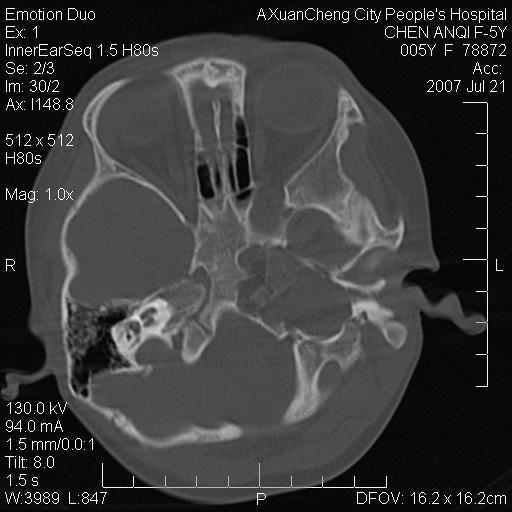

标题: PED0273:5岁,左耳流脓痛疼一周,颅底骨质破坏 [打印本页]

标题: PED0273:5岁,左耳流脓痛疼一周,颅底骨质破坏

患儿5岁,左耳流脓痛疼一周,左外耳道肉芽组织填塞 软组织窗显示病灶内结节状低密度影为气体密度

1.左耳中耳炎. 2.考虑伴颅内感染.

颅底骨质破坏,建议增强扫描

左侧中耳炎并胆脂瘤,左颞骨岩部骨质破坏并颅内感染积气。

补充:腺样体肥大.